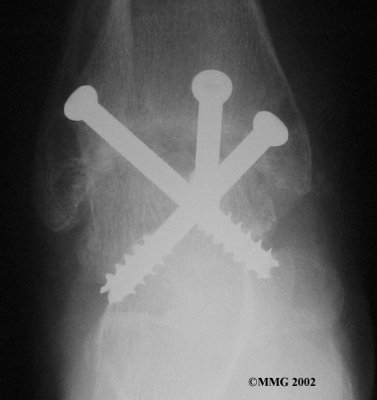

It is important when the surfaces are removed that the angles of the cut surfaces are correct. When the tibia is brought against the talus, the foot should be at a right angle to the lower leg. Once the cuts are made, the bones must be held in place while they fuse. This can be done using large metal screws and metal plates if necessary. The screws are usually under the skin and are not removed unless they begin to rub and cause pain.

Inserting the screws

After ankle fusion, the physical therapists at FYZICAL Gainesville can help you learn to walk smoothly and without a limp. Although time needed for recovery varies among patients, an ankle brace will typically replace your cast after eight to 12 weeks. Your surgeon will take X-rays frequently to see if the bones are fusing together. You will probably need to use crutches during the time you wear the cast. As the fusion grows stronger, you will begin to put more weight on your foot when walking.